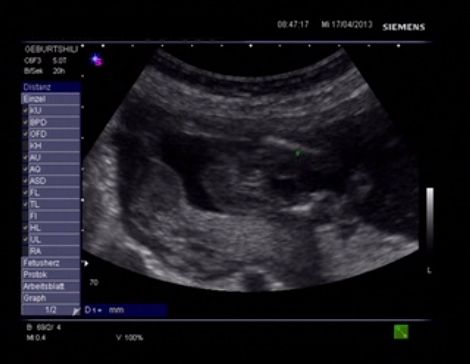

Hello Everyone! Its me again :-) A Gender swaying friend (wanting a Girl) made the The Baby Gender Predictor Test: Am I having a boy or girl? DNA - Test And it said -> BOY! Her second son is 19 Months old and she was pretty careful making the test... Now she went to her doctor’s appointment and the doctor was sure it’s a Girl!! What do you think? Picture 1 : (NT-Scan – Baby Nr.3 -> Is the current pregnancy ) Sohnemann 2 is her second Boy ;-) Picture 2: 17 weeks pregnant potty scan the arrow should show the girl parts .... So Ladys what do you think any chance itīs a GIRL??? Greetings & Thanks ....

Attachment 10345